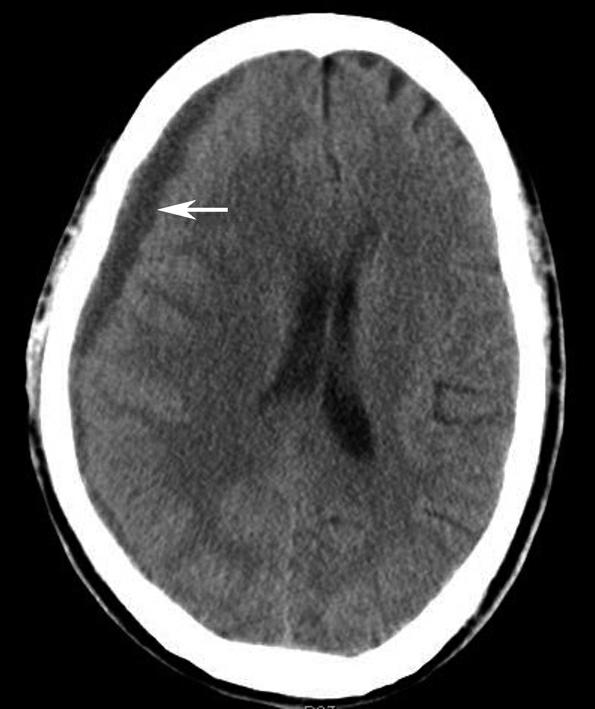

透明隔为两片膜状结构紧贴形成,之间有潜在腔隙,如扩大则形成透明隔腔,内含脑脊液样液体,称透明隔间腔或第五脑室,为正常变异(图1-2-37)。发育因素可导致双侧侧脑室的大小不对称(图1-2-38),一般无临床意义,但是需注意与病理性侧脑室不对称相鉴别(图1-2-39)。发育性因素导致的侧脑室不对称,脑实质及脑室内均无病变,且由大脑镰、透明隔等组成的中线结构无偏移。

图1-2-38 双侧侧脑室发育不对称

图1-2-39 病理性因素导致的双侧侧脑室不对称

A.右侧大脑半球转移瘤瘤周水肿(☆)引发的占位效应致右侧侧脑室明显受压变形、变小(箭),透明隔向左侧移位(箭头);B.左侧侧脑室旁陈旧性脑梗死、脑软化(☆),病灶体积缩小引发的负占位效应致左侧侧脑室体部外展、扩大(箭头)